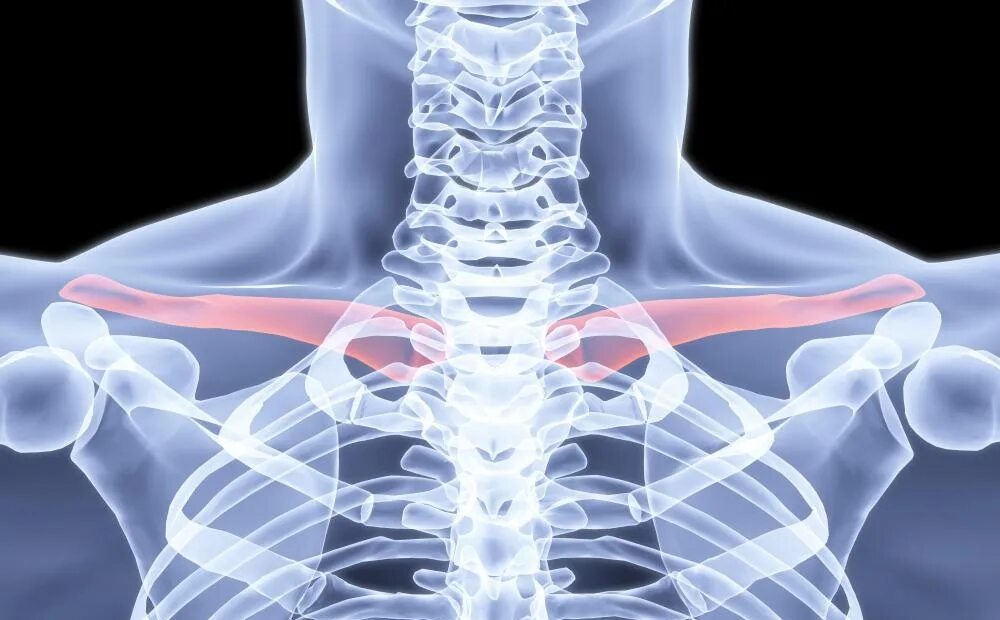

Хрустит ключица